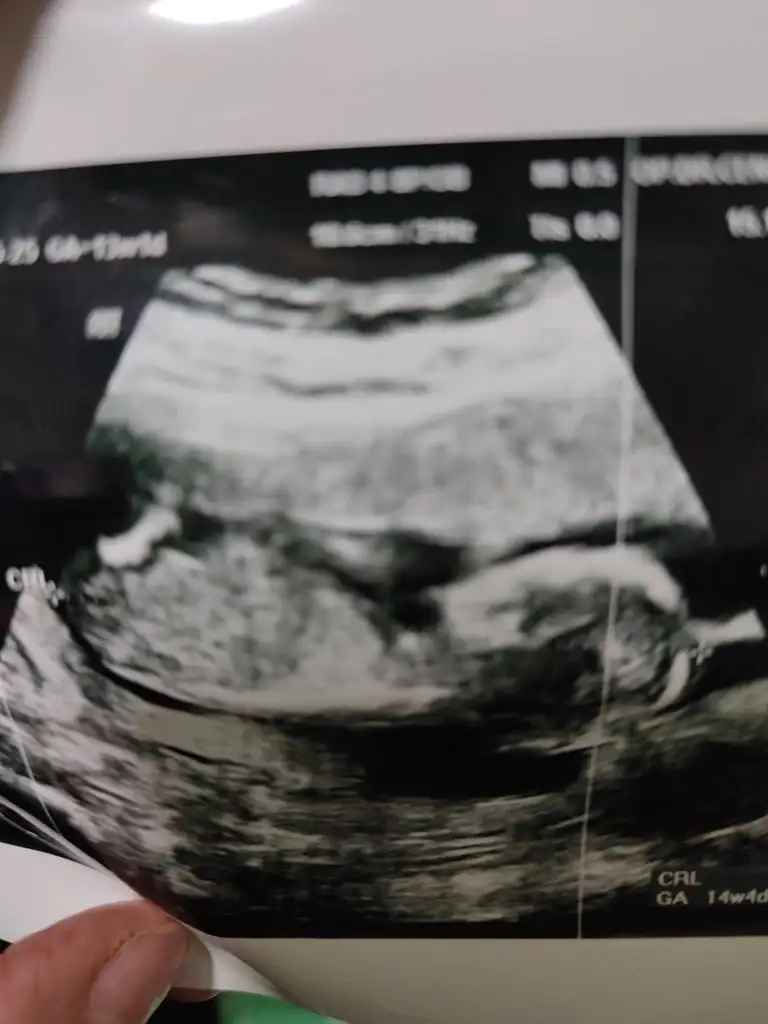

Bu haftalarda nub olmaz cnm 11 12 13 haftalar olmalı şekli kıza benzetimMerhabalar herkes sizi öneriyor bana da bir tanminde bulunur musunuz tam 14 haftalık ama kordon girdiği için emin olmamakla beraber erkek dendi içimden hep kız geçiyor rüya test vs ile cuma kesinleşecek ama sizden tahmin etmenizi istiyorum yardımcı olur musunuz

Canım 12+6 bu ultrason bakarsın cook sevinirim10 hafta uygun değil şimdilik kız yönünde ama en iyi 11 12 13 haftalar olmalı

Net değilCanım 12+6 bu ultrason bakarsın cook sevinirim